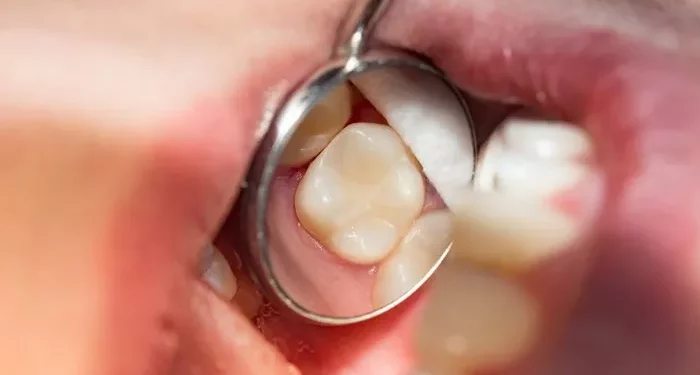

Cavities, also known as dental caries or tooth decay, are small holes that form in the enamel of a tooth. They are caused by the buildup of plaque, a sticky film of bacteria that forms on teeth. When we consume sugary or acidic foods, the bacteria in plaque produce acids that can erode tooth enamel. Over time, this process can lead to cavities.

Fillings are necessary when a dentist identifies a cavity during a dental examination. The dentist will assess the extent of the decay and determine the best course of action. If the cavity is small and has not progressed to the inner layers of the tooth, a filling may be sufficient. However, more extensive decay may require additional treatment, such as a crown or root canal.

The first step in the filling procedure is a dental examination. The dentist will use X-rays and visual inspection to determine the extent of the decay. If a cavity is found, the dentist will discuss the appropriate treatment options, including the type of filling material.